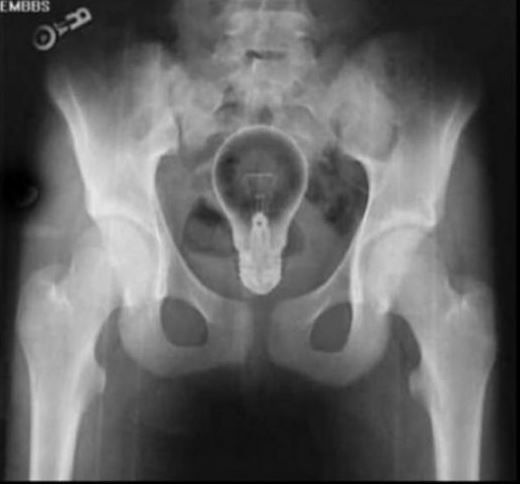

Doktorların görüp yok artık bu nasıl mümkün olur dedikleri röntgen filmleri..

Doktorluğun zor bir meslek olduğu malum. Üstelik bu mesleğin icra ederken bazı zamanlar öyle vakalar ortaya çıkmış ki, doktorlar bile anlamlandırmakta zorluk çekmişler.